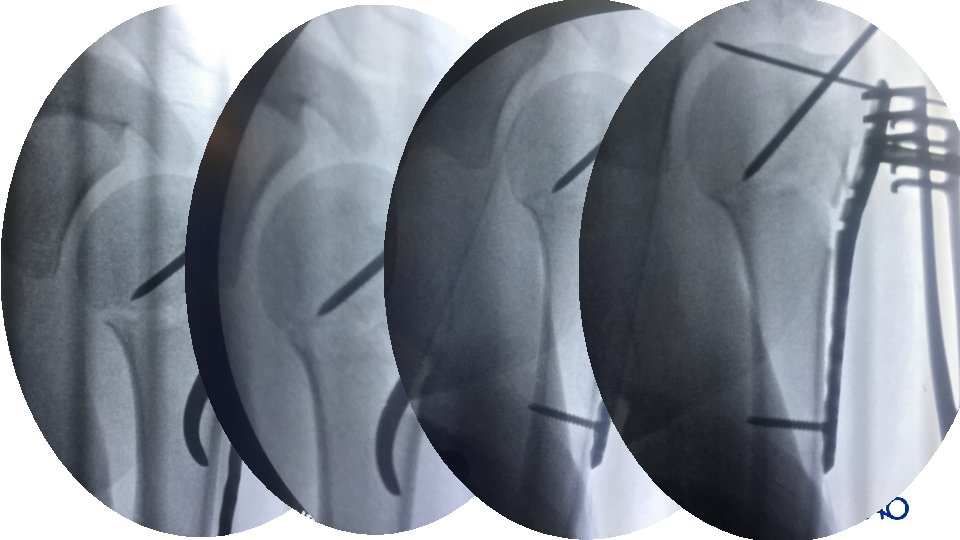

Reduction • • • Use direct or indirect Minimally invasive reduction could be achieved with K-wire joystick manipulation If not, go for open reduction

Specific fractures: type B and C • 36 -year-old man • 3 -part fracture dislocation

• Locked plate/screw and suture fixation • GT: sutures and screws oppose tension

• Locked plate/screw and suture fixation • GT: sutures and screws oppose tension • AN: buttress locked screws oppose compression

• • Locked plate/screw and suture fixation GT: sutures and screws oppose tension AN: buttress locked screws oppose compression SN: plate for varus/torsion control